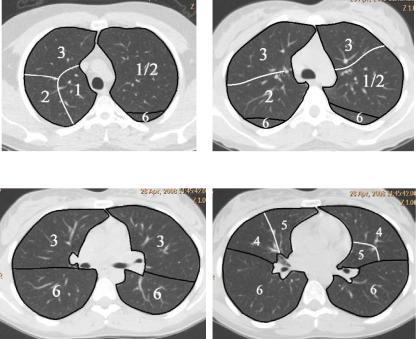

Анатомические изображения сегментов легких различных животных

Раздел: Другие животные